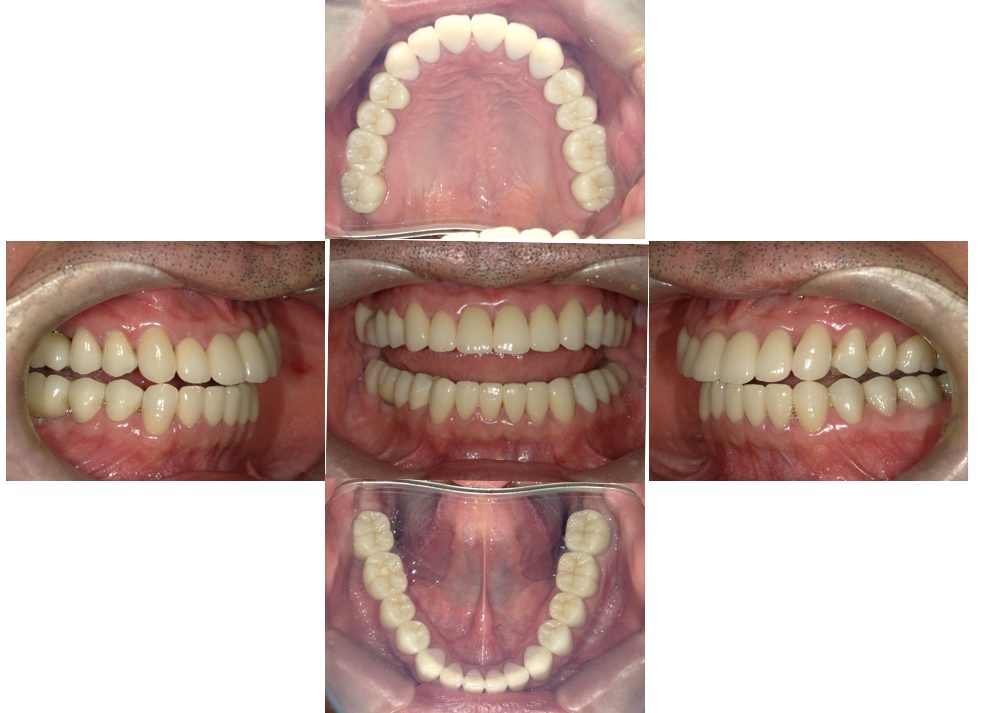

セラミック治療 (メタルフリー治療)の症例紹介②(三隅歯科クリニック)

三隅 賢祐(三隅歯科クリニック)

症例詳細

| 主訴 | 金属の被せ物をセラミックにしたい |

| 治療内容 | インプラント治療、セラミック治療、金属床コーヌス義歯(部分入れ歯)を行いました。 |

| 治療費 | 1,600,000円(税込み) |

| 治療期間 | 4か月 |

| 治療回数 | 3回 |

| 想定されたリスク | 残存歯の土台となる歯に変色がある場合は透けて見える可能性があった |